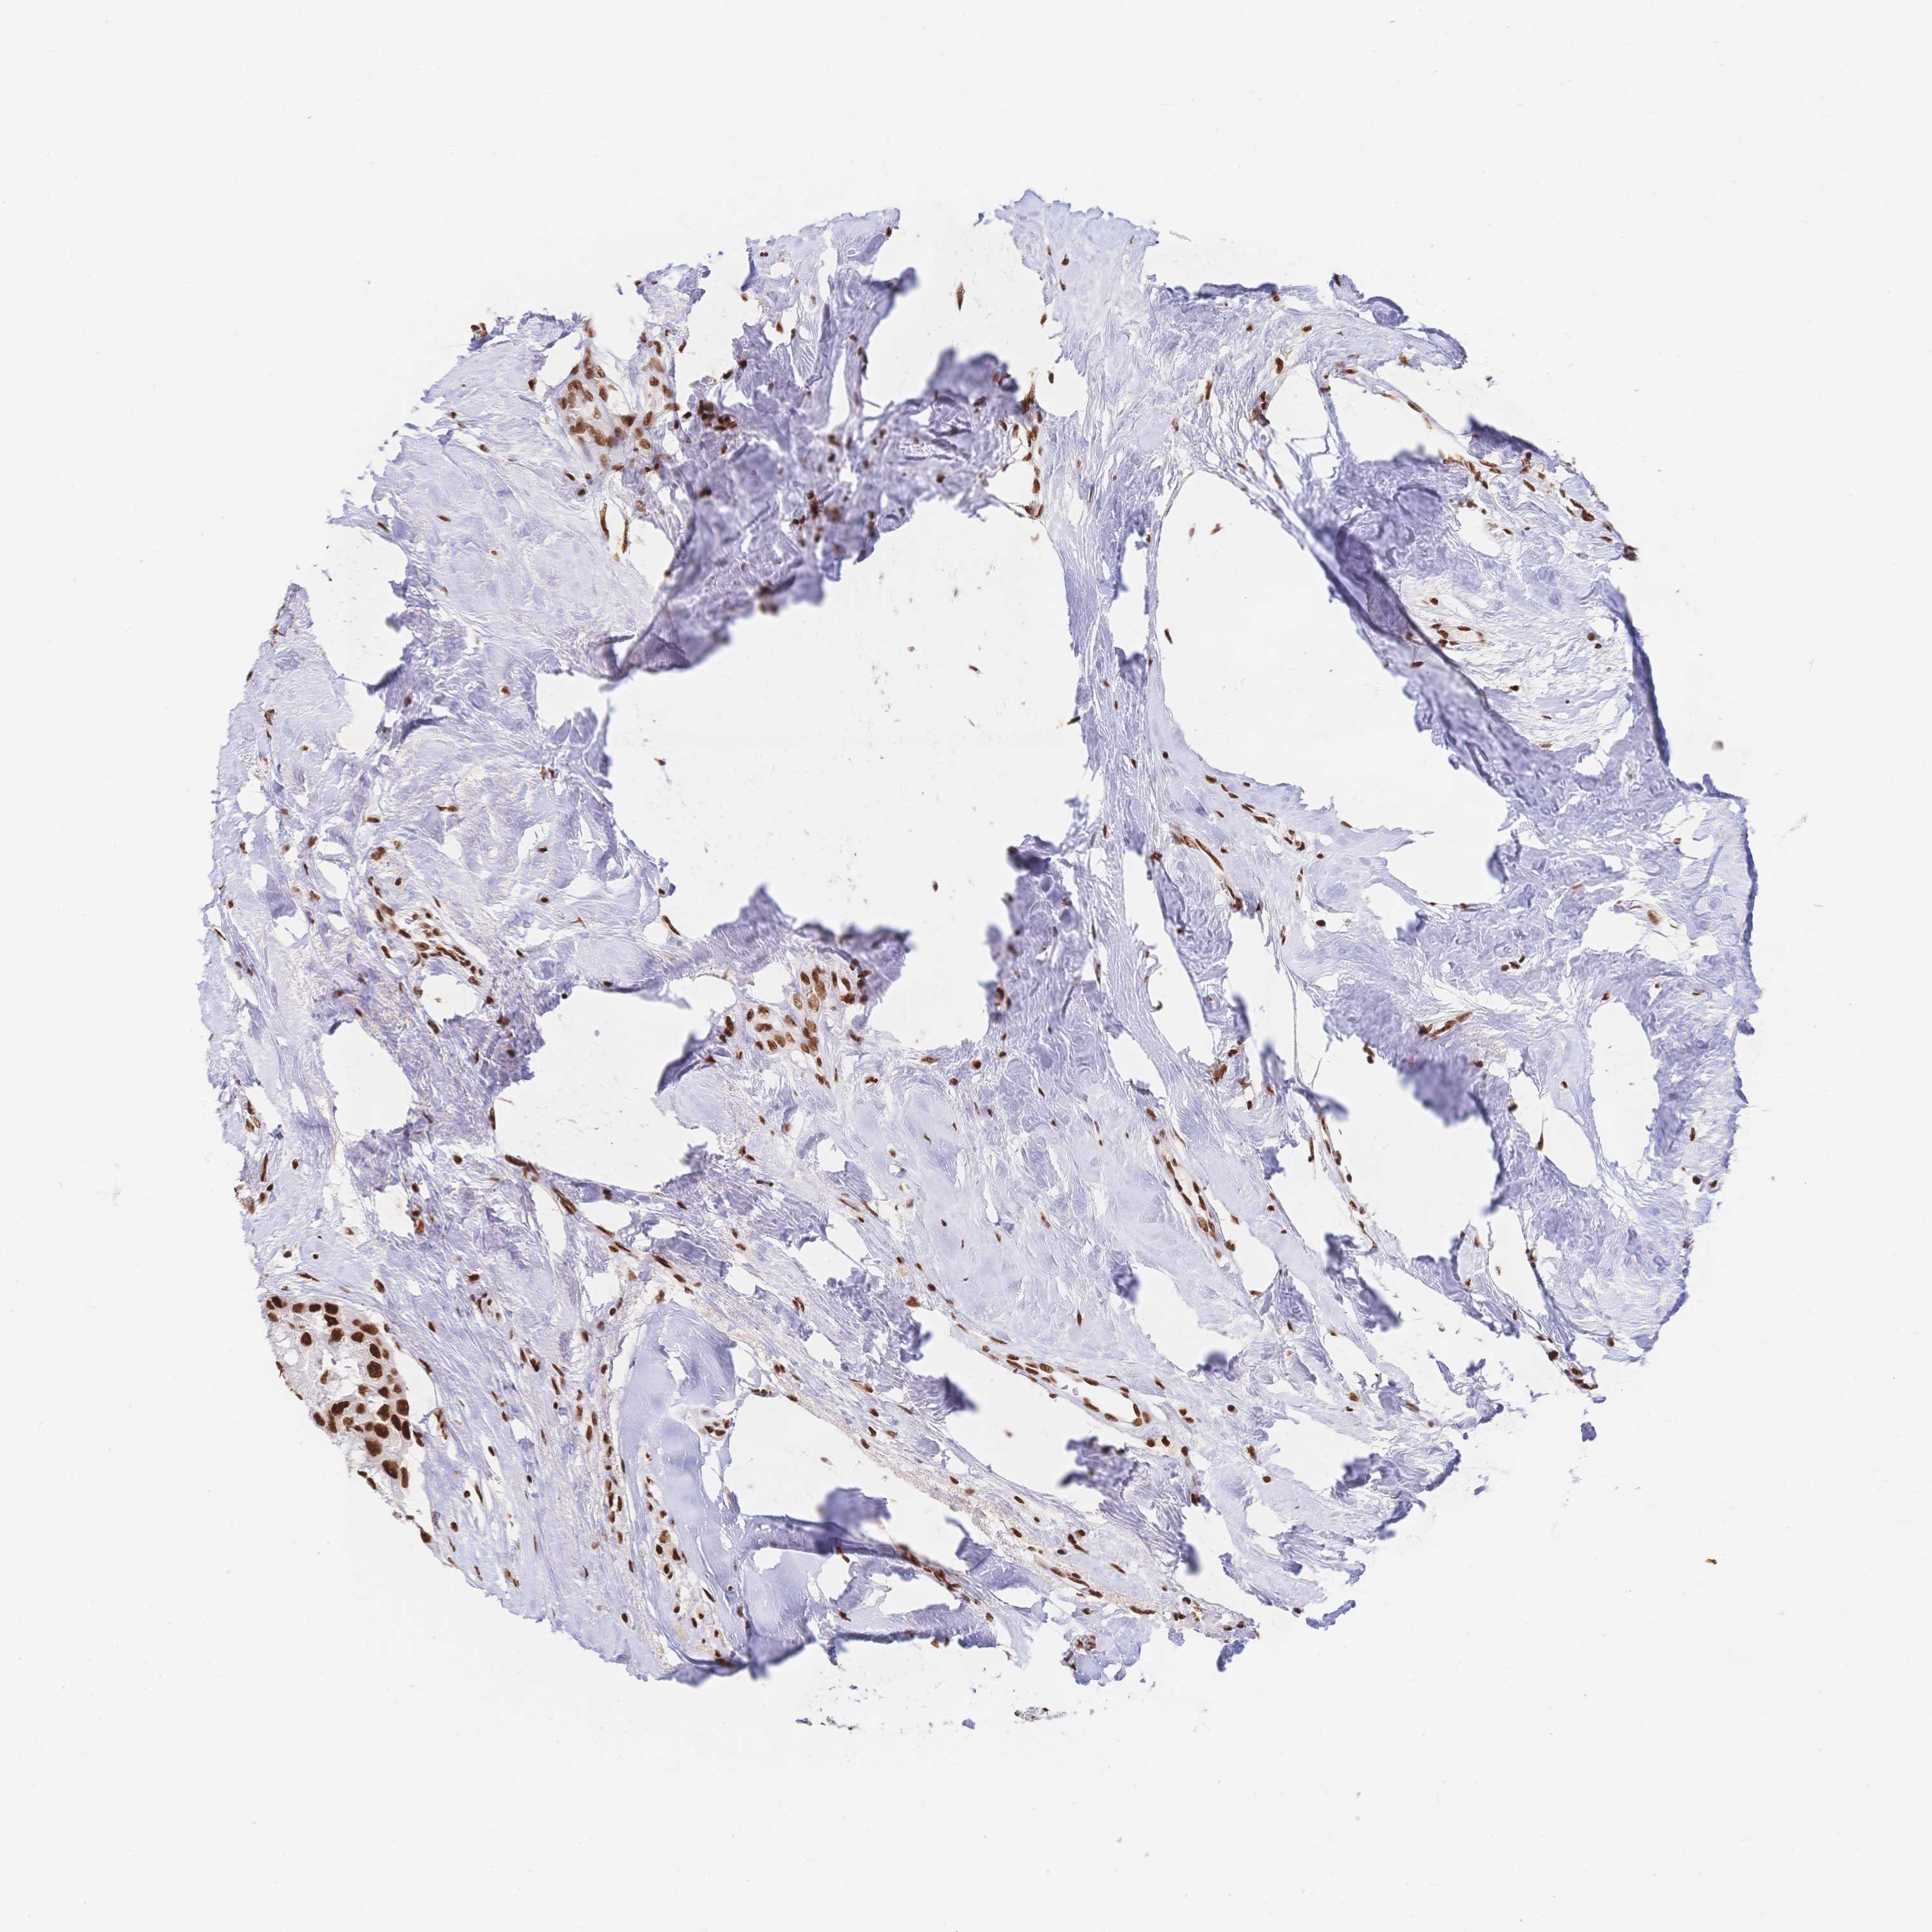

SRSF1

CANCER BREAST CANCER Show tissue menu

BRCA TCGA BRCA VALIDATION PROTEIN EXPRESSION

Breast cancer

Human cancer

SRSF1 is not prognostic in Breast Invasive Carcinoma (TCGA)